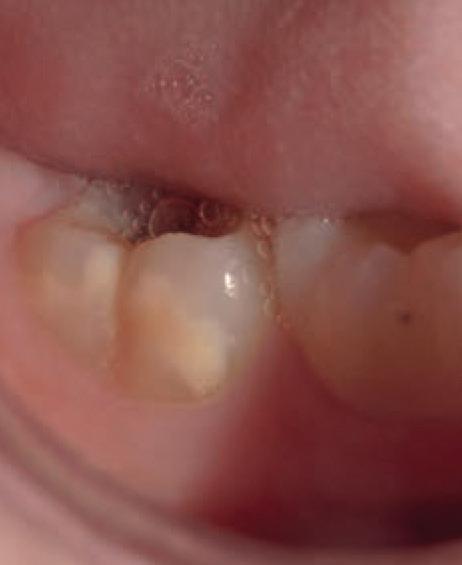

SYNTHETIC MONOFILAMENT SUTURES MADE FROM A COPOLYMER OF POLYGLYCOLIC ACID AND POLYCAPROLACTONE (PGCL).

Photos courtesy of Prof Dr Rocio Lazo (Peru)